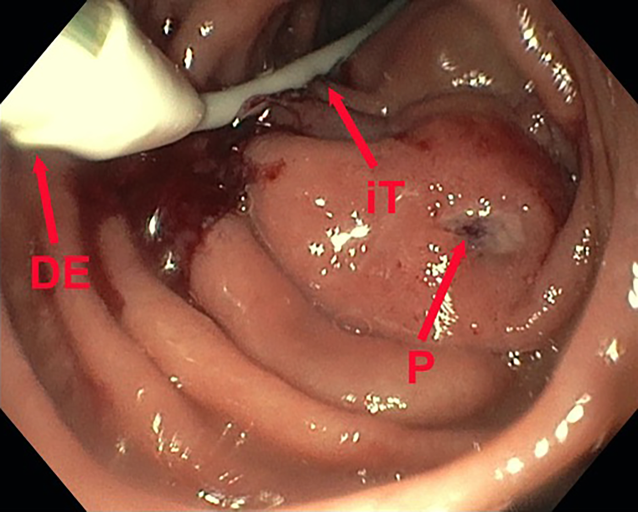

Die dOFD hat einen Durchmesser von nur 6 mm. Die transnasale Einführung erfolgte unter endoskopischer Sicht in gleicher Technik wie bei einer gastroduodenalen Ableitsonde. Der intestinale Ernährungsschenkel der dOFD wurde endoskopisch entlang des Pylorus in das Duodenum vorgeschoben und die dOFD mit dem offenporigen Folienabschnitt durch weiteres Vorschieben tief im Duodenum, die Defektregion überdeckend, platziert (Abb. 3).

Abb. 3

Platzierungsmanöver der dOFD. Ernährungssonde (iT), Übergang zum folienummantelten Abschnitt (DE), übernähter Perforationsdefekt (P) des Nephrostomiekatheters mit perifokalem Ödem und lokalen Entzündungszeichen